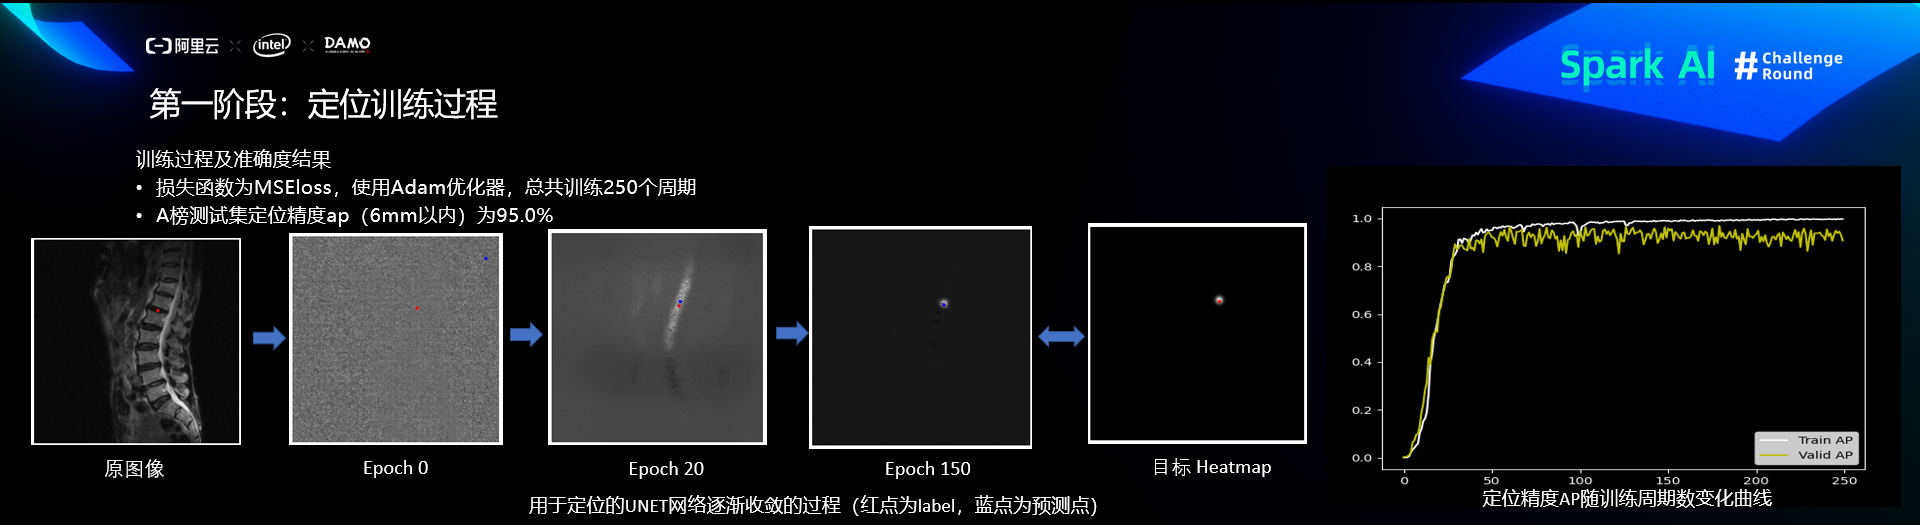

第一阶段:定位

定位训练过程